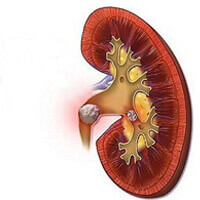

- KARACİĞERDEN TOKSİNLERİ ATAR, KARACİĞER ENZİMLERİNİ DÜŞÜRÜR

- Oksidatif stresi azaltır, iltihaplanmayı azaltır, böbrek fibrozisiyle savaşır

Piyasadaki çoğu antidiyabet ürünü sadece belirtileri yok ediyor, sorunun sebebini değil. Dianon diyabet kontrolünde mükemmel, sürdürülebilir bir etki sağlıyor. Bir kür sonrasında diyabet giderek yok oluyor, tüm vücut fonksiyonları geri kazanılıyor bozukluklar ve metabolizma bozuklukları tamamen düzeliyor.